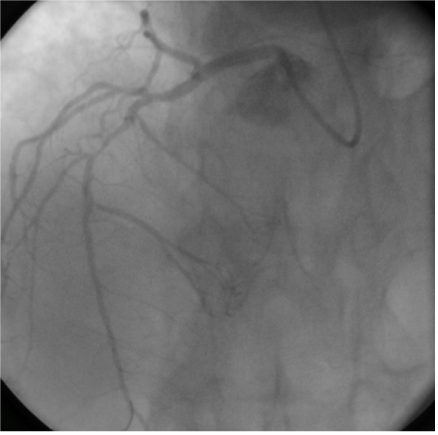

A 55-year old man was transferred from one of our referring hospitals with early post infarct unstable angina, having chest pain in the right side of the chest radiating to the right shoulder and the back, following an anterior ST-elevation myocardial infarction for which he had received thrombolytic therapy. He was a known case of dextrocardia with Kartagener syndrome, diabetic and smoker. Physical examination was unremarkable except for findings consistent with dextrocardia. Apart from raised troponine-I and blood sugar, his routine laboratory tests were within normal values. 12-lead Electrocardiogram (ECG) showed a negative P wave lead-I and aVL and positive P and R waves in aVR together with Q waves in inferior leads. Reversed chest leads showed QS in V1-V3 with ST depression in V4-V6 associated with deep T wave inversion. Chest X-ray revealed dextrocardia with a right-sided aortic knob as well as gastric bubble. Echocardiography revealed left ventricle ejection fraction of 40% with hypokineses correspondent with ischemia in left anterior descending artery (LAD) territories and no significant valve disease. Cardiac catheterization was performed via the right radial artery using mirror-image views and standard Judkins catheters. A 5 French (Fr) angulated pigtail catheter was through the right-sided aortic knob into the left ventricle. The 300 left anterior oblique (LAO) ventriculogram (Figure 1) showed anterior wall hypokinesia and severe hypokises/akineses of the apex and the inferior wall with an ejection fraction of 40%. The ostium of the right coronary artery (RCA) was easily engaged by gentle counterclockwise rotation and slightly withdrawal of a 5 Fr Judkins right 4 cm (JR4) diagnostic catheter in right-anterior-oblique (RAO) and RAO-cranial views showed 100% lesion at mid-RCA segment (Figure 2). The ostium of the left main coronary artery was also cannulated using a 5 Fr Judkins left 4-cm (JL4) diagnostic catheter in a RAO view. The selective left coronary angiogram revealed a>70% tubular stenosis in the middle segment of LAD artery and a patent left circumflex (LCX) artery (Figure 3). Adhoc-PCI to LAD was performed with the use of 5 Fr JL 3.5 guide catheter and a 0.014” balanced middleweight (BMW) guide wire. Two overlapping drug-eluting stents (Xience Prime 2.5x28mm and Promus Element 2.25x12mm) were directly deployed at the site of the lesion in the middle segment of the LAD artery with good angiographic result (Figure 4). The patient experienced an uneventful post-PCI course and was discharged on the following day. He was free of angina on clinical follow-up.

Figure 1 Left ventricle angiogram in left anterior oblique view 30˚ showing mirror image anatomical configuration of the left ventricle in conventional right anterior oblique 30˚ view.